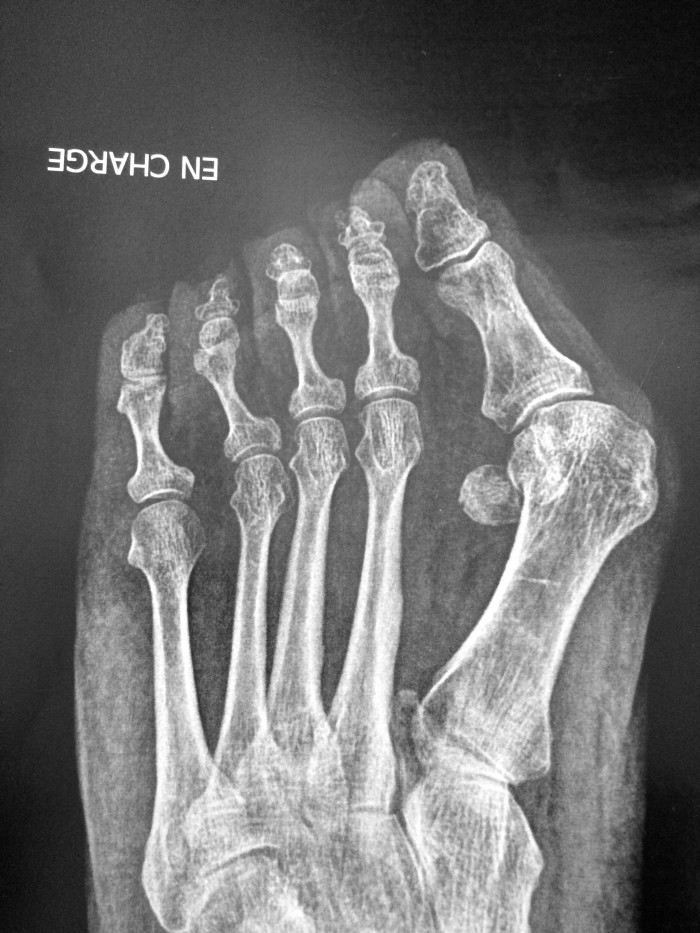

Рентген после операции Hallux valgus